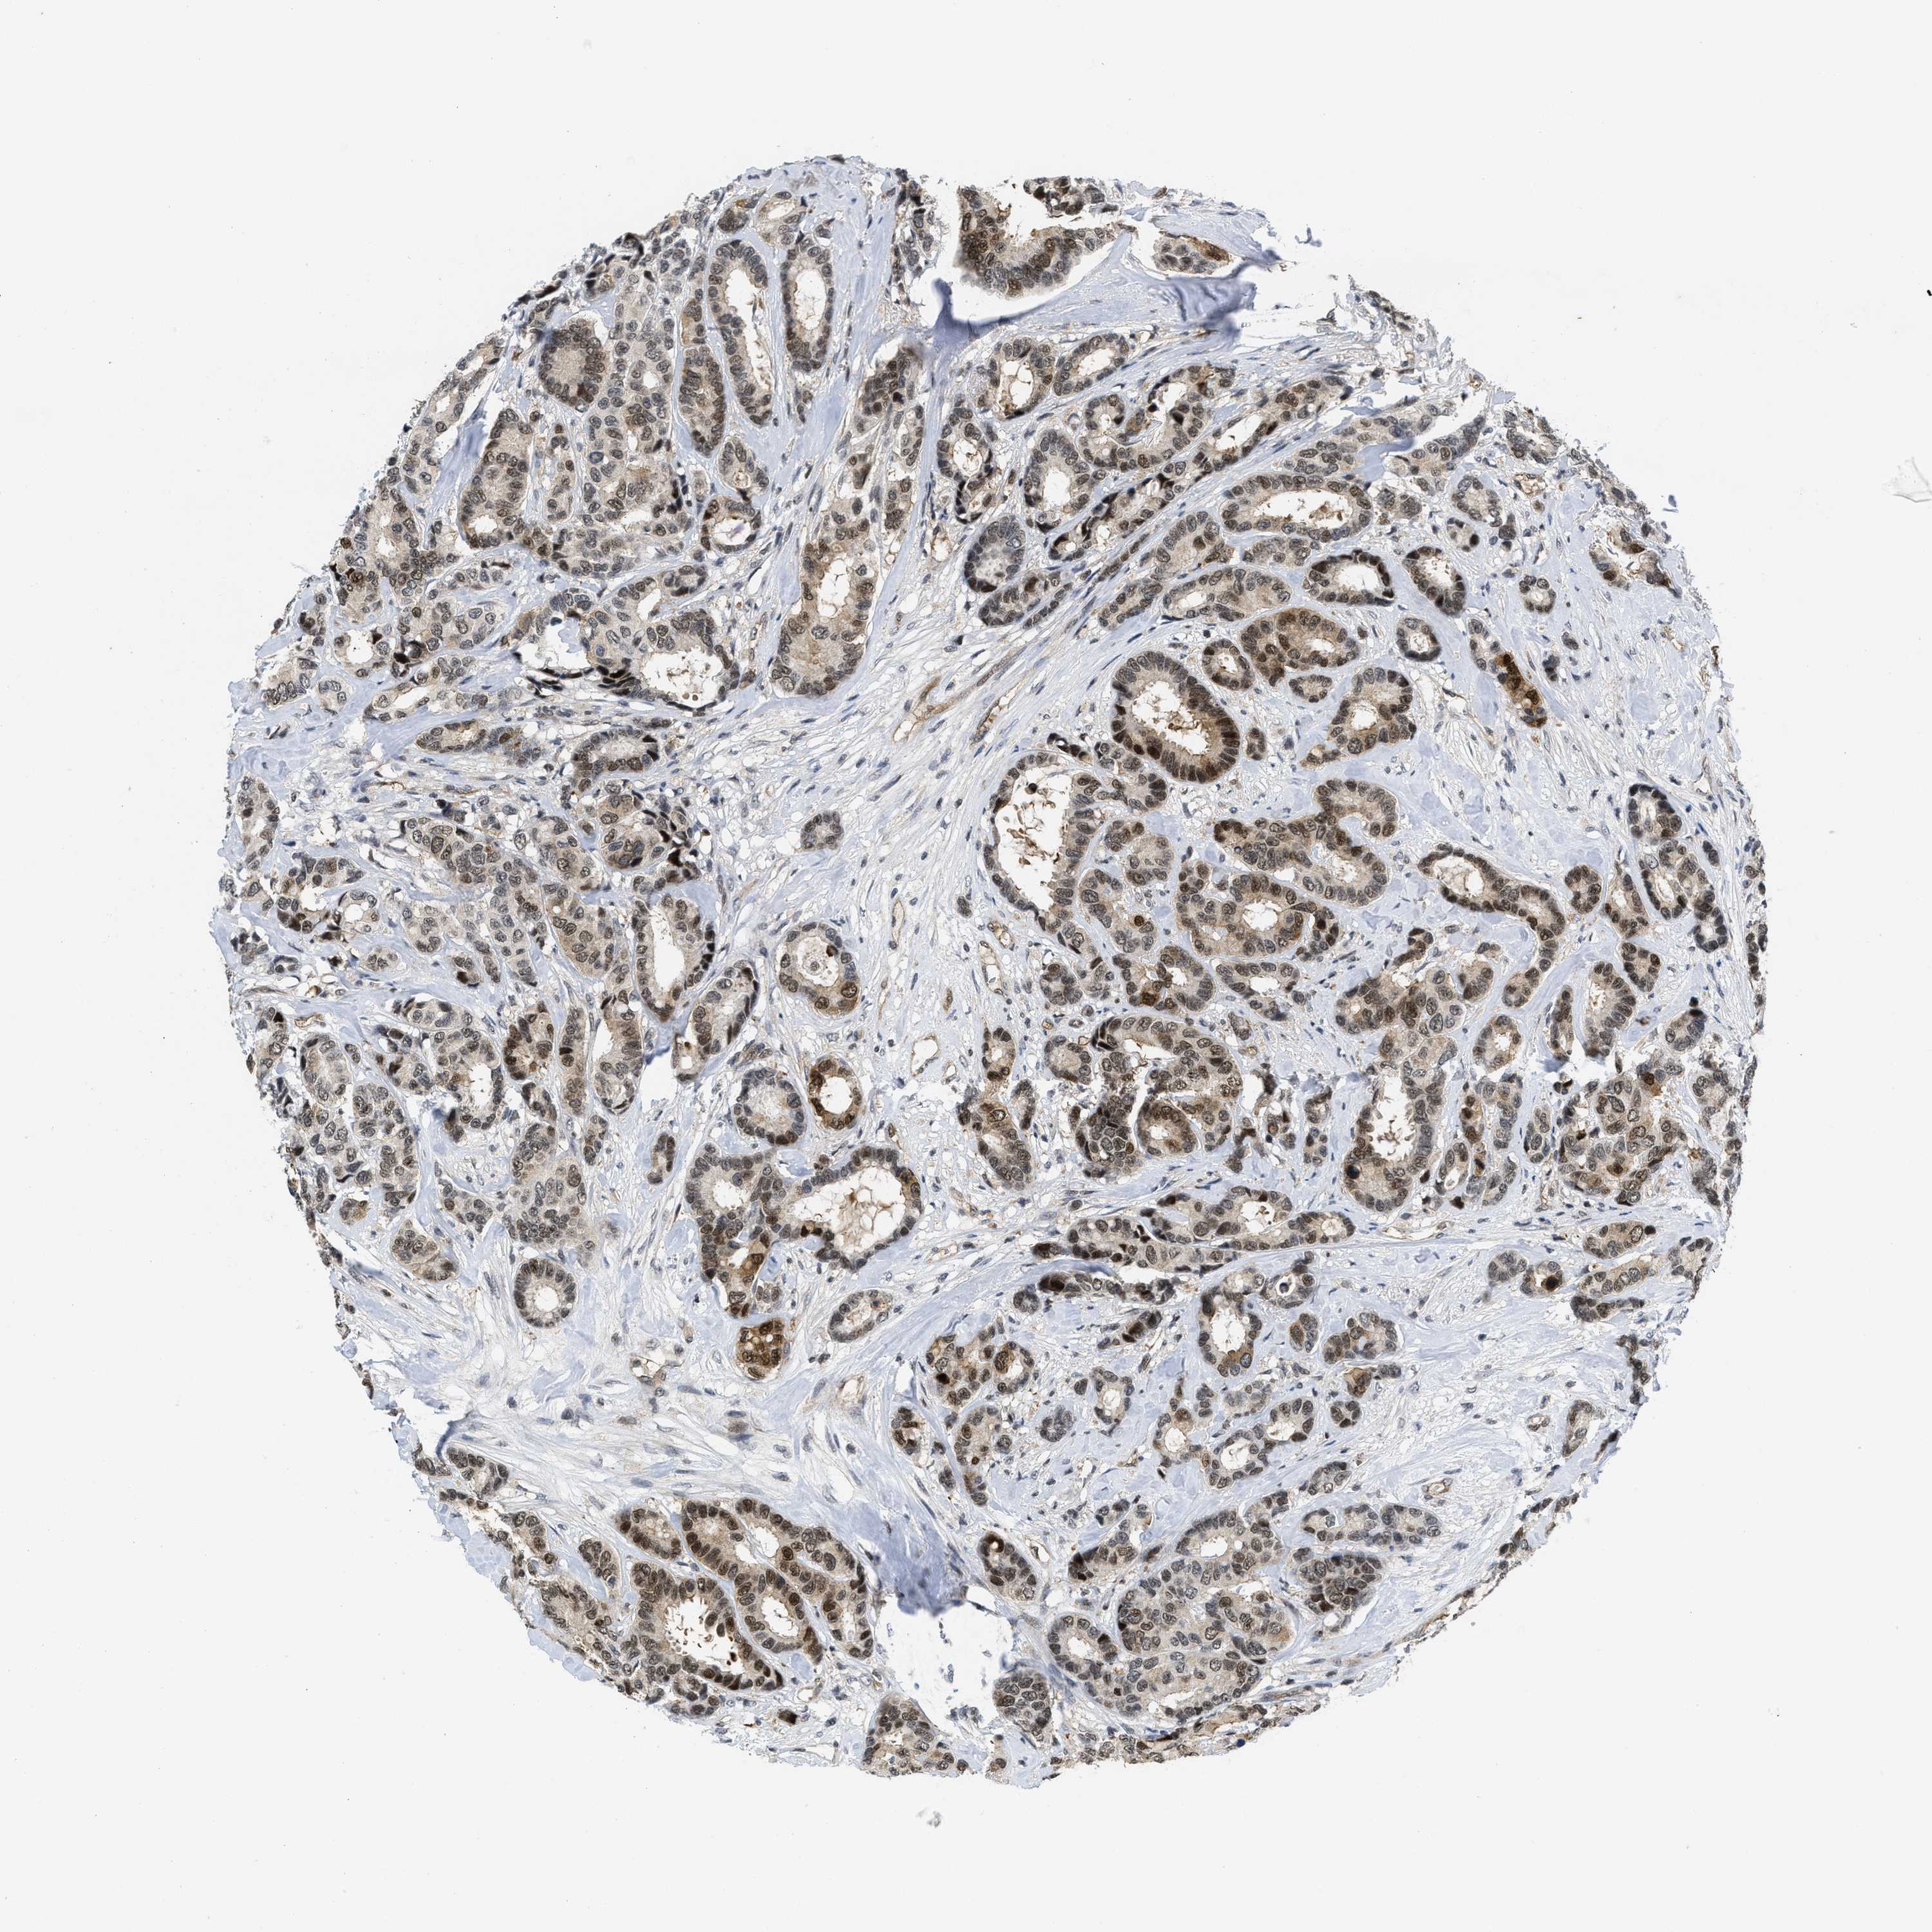

CANCER BREAST CANCER Show tissue menu

BRCA TCGA BRCA VALIDATION PROTEIN EXPRESSION